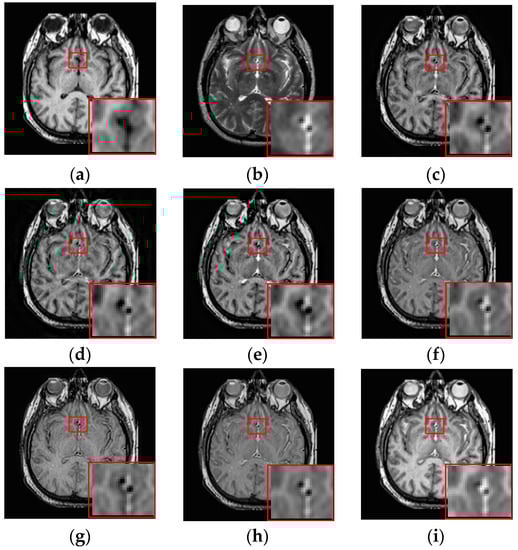

To further demonstrate that the proposed method is equally effective for other types of medical image fusion, we test the other two categories of medical image fusion systems include MRI/SPECT and MRI/PET, and the fusion results are shown in Figure 9 and Figure 10. The details of fused images are zoomed in and presented in the bottom left corners of their respective images.

Figure 9.

Fused results of MRI/SPECT medical images by different methods. (a) MRI; (b) SPECT; (c) DCTWT; (d) Curvelet; (e) NSCT; (f) Liu-ASR; (g) Kim; (h) Zhu; (i) Proposed.

Figure 10.

Fused results of MRI/PET medical images by different methods. (a) MRI; (b) PET; (c) DCTWT; (d) Curvelet; (e) NSCT; (f) Liu-ASR; (g) Kim; (h) Zhu; (i) Proposed.

With more careful observation, we can see that the spatial edge details and brightness information in Figure 9i and Figure 10i are more accurate compared with Figure 9c–h and Figure 10c–h generated by the six compared methods. This means the useful information from source images have been successfully transformed into the fused images, that is, our fused results have the best visual features. This is mainly because the novel construction of the overcomplete dictionary in this paper is composed of two parts include the brightness sub-dictionary and the edge detail sub-dictionary, which can fully express the significant features of the medical images. This will be very beneficial to the implementation of medical image fusion in practical medical assistance applications. In conclusion, the proposed algorithm has the best subjective visual effect.